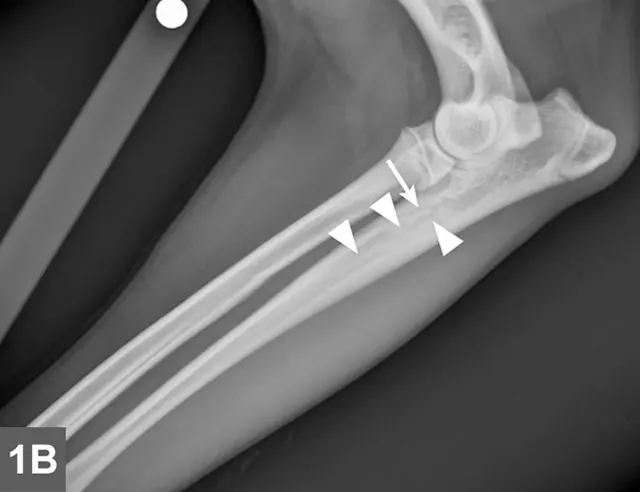

Radiographic signs of panosteitis frequently lag days to weeks behind clinical signs.1,3 The earliest radiographic sign of panosteitis is a decrease in opacity around the nutrient foramen. Later signs include an increase in mineral opacity within the medullary canal of long bones and loss of the normal trabecular bone pattern (Figure 1). Smooth periosteal and endosteal new bone may also be seen in more severe cases (Figure 2). Radiographs of the affected limb may be compared with those of the contralateral limb to assist in diagnosis. Nuclear scintigraphy may assist in diagnosis in cases in which radiographic changes have not yet developed.4

FIGURE 1A

Lateral radiographic projections of the femur (A) and ulna (B, next slide) in dogs with early signs of panosteitis. Note the radiolucency around the nutrient foramen (arrows) and increased opacity within the medullary canal (arrowheads) in both cases.